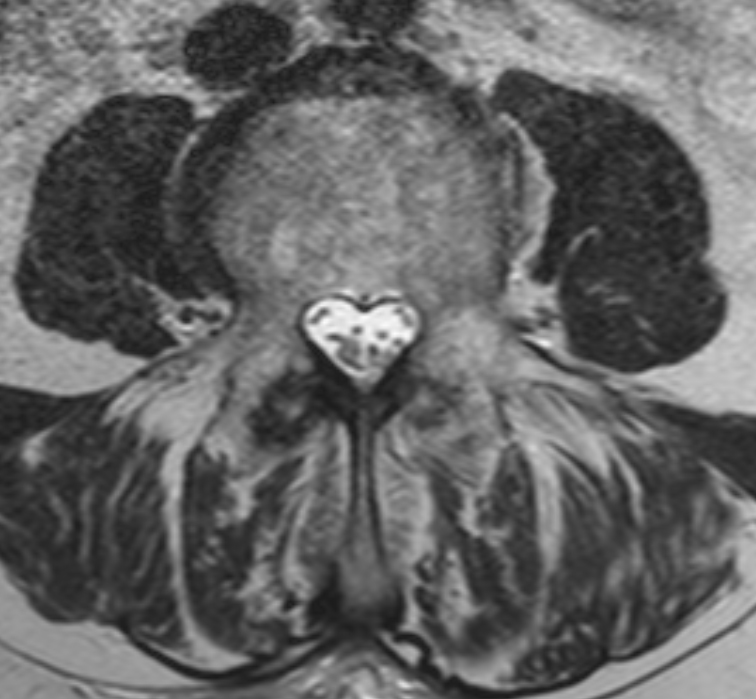

Système ventriculaire

Belles images

La magie de l'imagerie